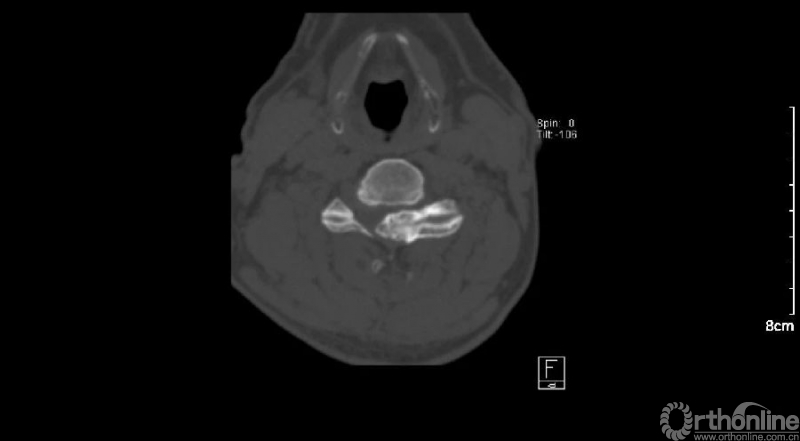

入院查体患者四肢肌张力高,双侧hoffman阳性。CT及MRI检查提示C4/5左侧关节突内缘有一巨大骨块(15mm*16mm),相应节段椎管严重狭窄。椎管内骨块的前端还有一游离骨块。

影像学资料